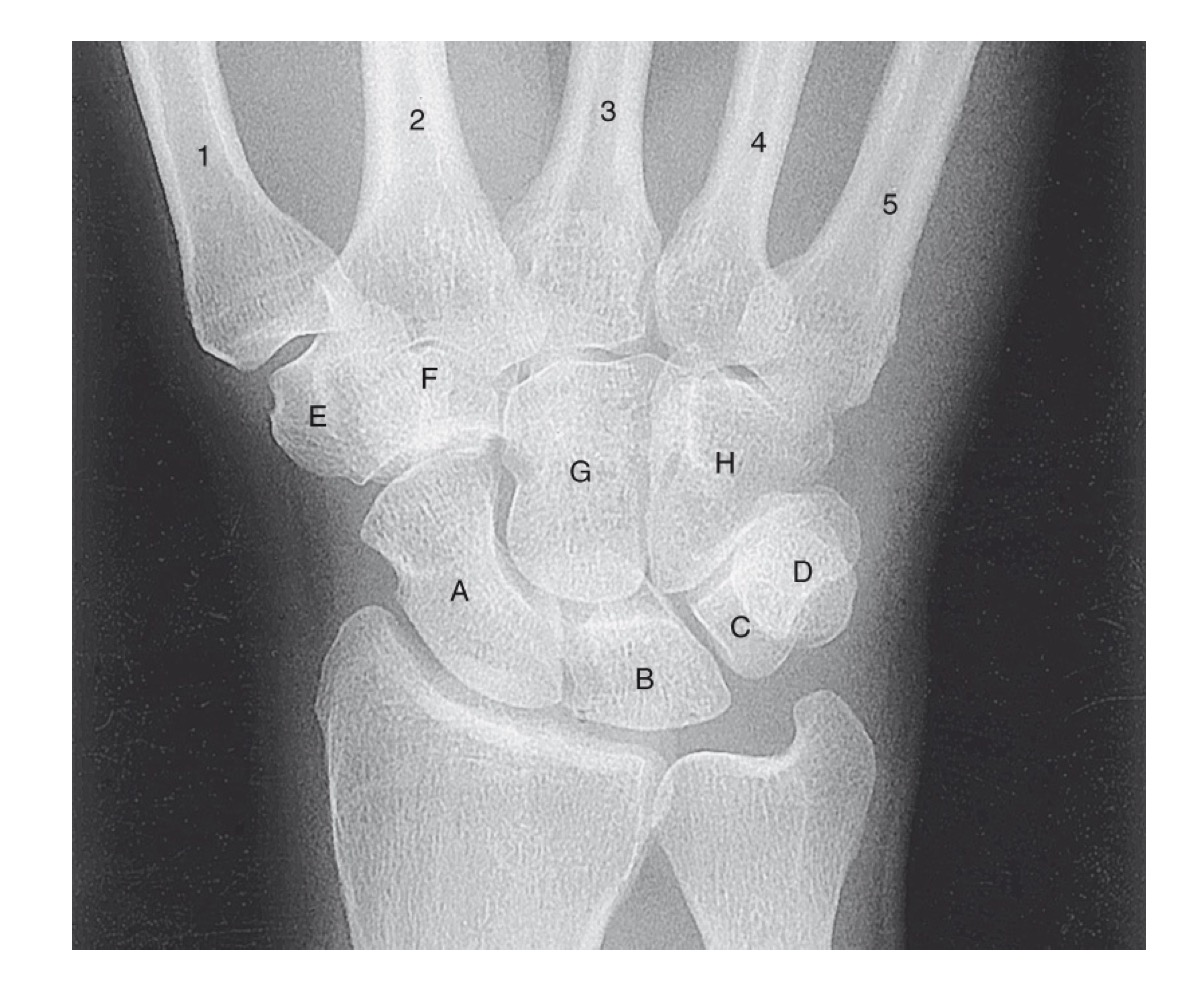

<p>identify A</p>

identify A

first carpometacarpal

14

New cards

<p>B?</p>

B?

first metacarpal

15

<p>C?</p>

C?

first metacarpophalangeal joint

16

<p>D?</p>

D?

proximal phalanx of the first digit

17

<p>E?</p>

E?

interphalangeal joint of the first digit

18

<p>F?</p>

F?

distal phalanx of the first digit

19

<p>G?</p>

G?

second metacarpophalangeal joint

20

<p>H?</p>

H?

proximal phalanx of the second digit

21

<p>I?</p>

I?

proximal interphalangeal joint of the second digit

22

<p>J?</p>

J?

middle phalanx of second digit

23

<p>K?</p>

K?

distal interphalangeal joint of second digit

24

<p>L?</p>

L?

distal phalanx of second digit

25

<p>M?</p>

M?

middle phalanx of the fourth digit

26

<p>N?</p>

N?

distal interphalangeal joint of fifth digit

27

<p>O?</p>

O?

proximal phalanx of third digit

28

<p>P?</p>

P?

fifth metacarpophalangeal joint

29

<p>Q?</p>

Q?

fourth metacarpal

30

<p>R?</p>

R?

fifth carpometacarpal joint